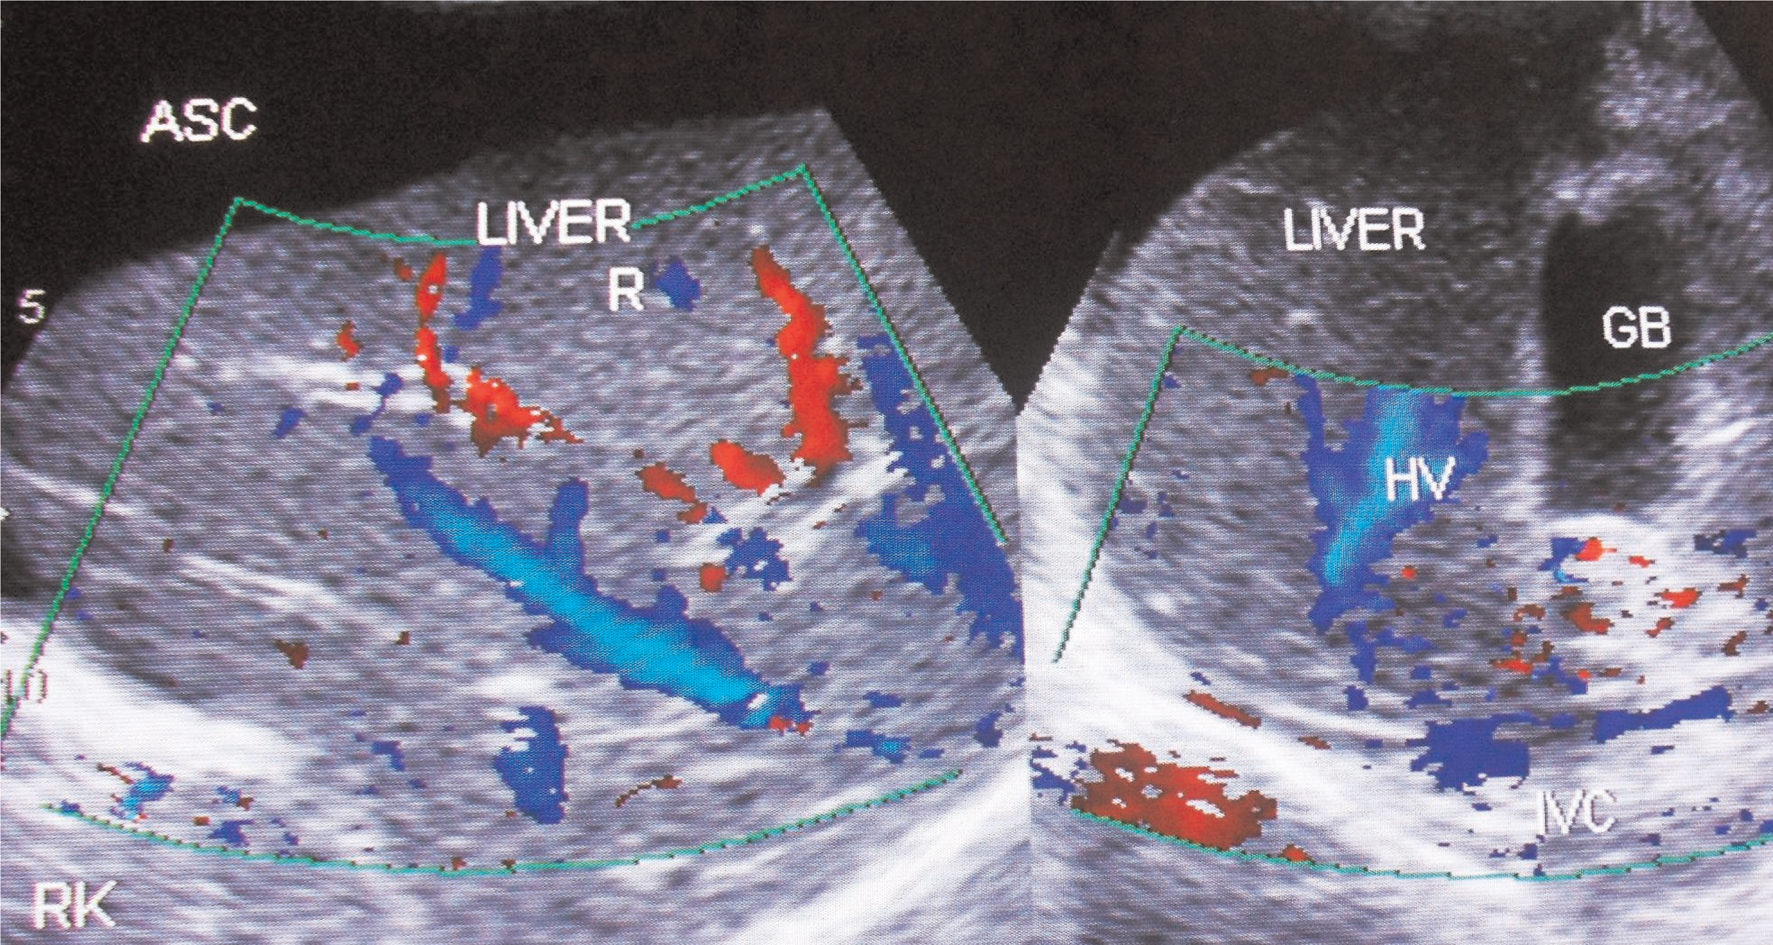

Fig 6

Figure 6. Ultrasonography and color Doppler of a patient with ascites due to HVCS. IVC shows stenosis at cavo-atrial junction with distal segment dilated. IVC is filled with organized thrombus. There is obstruction to blood flow at the hepatic vein outlets. Note thrombosis of medium-sized tributaries of right hepatic vein. GB, gall bladder; HV, hepatic vein; RHV, right hepatic vein. (Copyright: Santosh Man Shrestha).

Acute onset of high-protein-content ascites in young female patients, especially Caucasians with risk factor for thrombosis, is likely to be due to BCS. BCS patients with myeloproliferative disorders have, on average, higher platelet counts and a larger spleen. US/CD imaging of liver will show features of HV obstruction similar to HVCS, but IVC will be normal or narrowed by caudate lobe enlargement without organized thrombus along its posterior wall, bacterial peritonitis or edematous gallbladder wall.